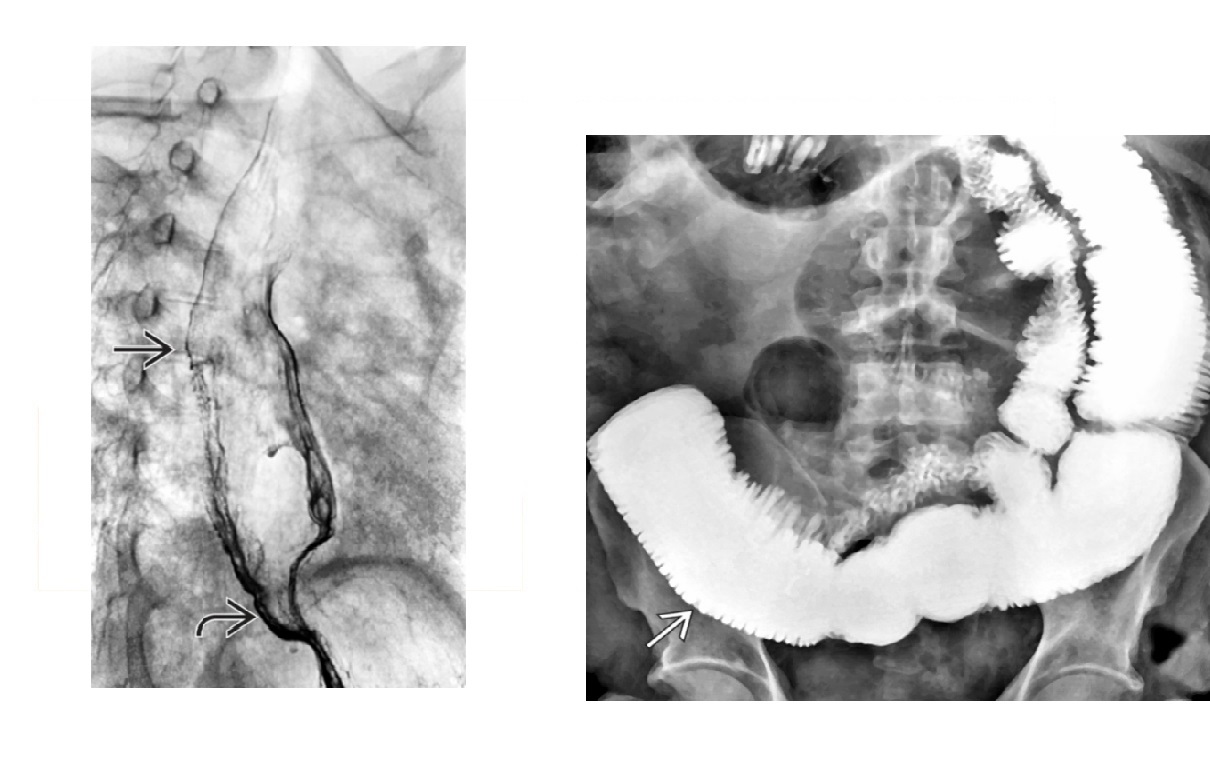

DDx for stenois of terminal ileum and features?

Crohn disease Yersina gram-negative bacterium, radiographic similar to Crohn's. resolves quickly, without stricture TB -Asymmetric wall thickening of ileocecal valve and - Cecum and terminal ileum are usually contracted (**cone-shaped cecum)** - nb Crohn's not typical for caecum -Look for signs of peritonitis/ ascites & caseated nodes - ** large linear Ulcers with elevated margins ** - Fleischner/umbrella - narrowed TI and open ileocecal valve Carcinoid Mesenteric mass (± calcification)/ desmoplastic infiltration of SB mesentery